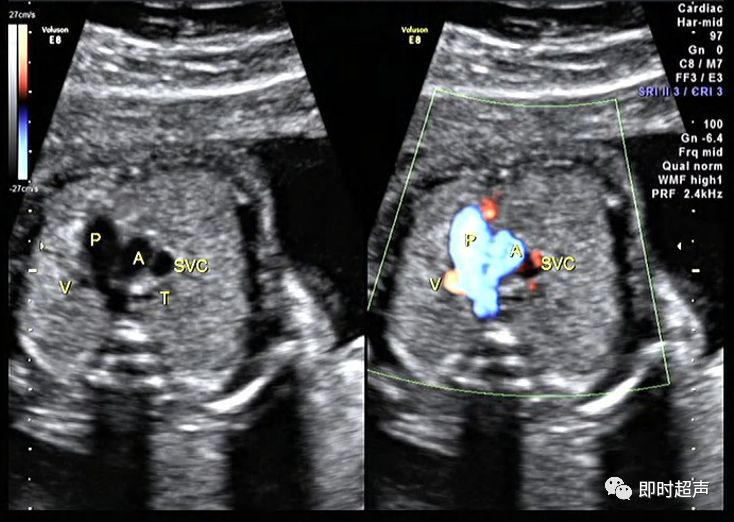

二、血管数目增多2

- 迷走右锁骨下动脉

- 正常的奇静脉

- 下腔静脉离断伴

奇静脉连接

正常奇静脉

迷走右锁骨下动脉

如何鉴别奇静脉和迷走右锁骨下动脉

- 多普勒频谱

- 观察清楚起止部位